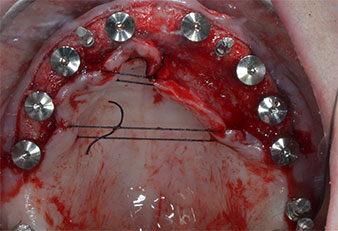

Три години по-късно е дошло времето за максиларна протеза от същия тип. Въз основа на планирането със CBCT, аугментацията на синусите е избегната с помощта на къси импланти и използването на хирургичен шаблон, за да се прехвърлят планираните позиции в алвеоларния гребен. (Фиг. 1 и 2).

Пиезоелектрически инструмент с диамантено покритие с форма на пламък (Piezomed I1) e използван за маркиране на позициите на имплантите и за пилотна подготовка (Фиг. 3). Препарацията беше извършена с внимателни вертикални движения, с намалена мощност, пълна иригация и лек натиск (под 300 g) След това се приложи пилотен инструмент (Piezomed I2A/ I2P) за първоначално увеличение на диаметъра на имплантното ложе с 2 mm (Фиг. 4), последвано от 3 mm разширение (Фиг. 5)

Поради сравнително твърдата кост (D2) в тази област, 10-милиметровото имплантно ложе в позиции 11 и 21 беше завършено с ротационен дрил с диаметър 4 mm в комбинация с W&H хирургичен обратен наконечник WS-75 L, W&H имплантологичен мотор Implantmed и опционалния W&H Osstell ISQ модул. За разлика от това, благодарение на меката кост, дисталните зони се подготвят до окончателен диаметър 3 mm, използвайки накрайник за Piezomed I3P. Имплантите най-накрая са поставени трансгингивално, за да остеоинтегрират за три месеца (Фиг. 6-10). Съществуващата протеза се фиксира на четирите временни импланта (Фиг. 8).